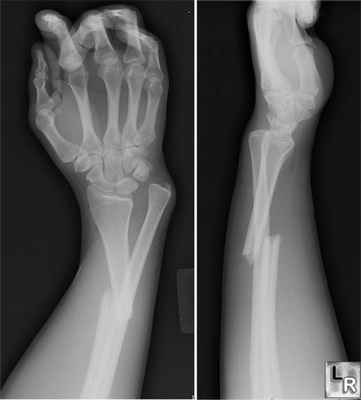

106. Переломы дистального отдела костей предплечья

Остеосинтез при переломах дистального отдела лучевой кости производят редко, как правило, при неудаче консервативного лечения. Для остеосинтеза применяют малую Т-образную пластину (Рис. 140).

Первый винт вводят через продолговатое отверстие в проксимальный отломок, тем самым создавая опору для дистального фрагмента. Сам отломок фиксируют компрессионным спонгиозным винтом через отверстие пластины. Рану ушивают с тщательным восстановлением квадратного пронатора. Движения в лучезапястном суставе разрешают через 3–5 дней.

Остеосинтез лучевой кости в дистальном отделе

Вешняя фиксация при переломе лучевой кости в типичном месте.